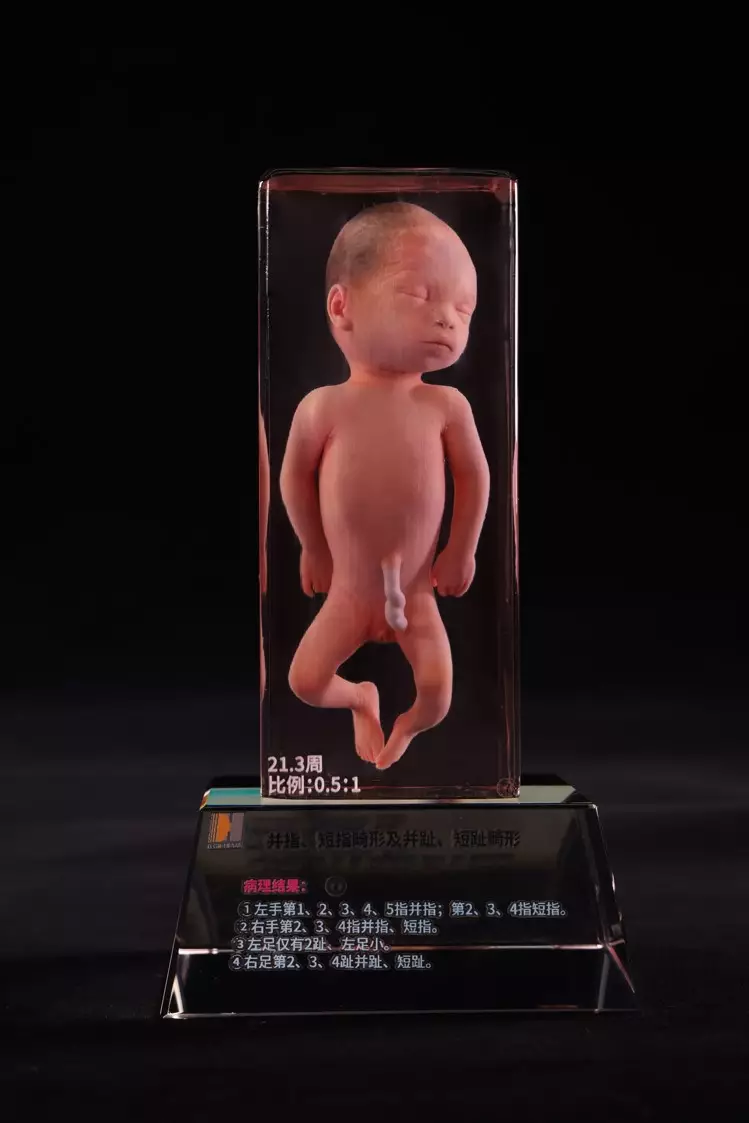

Human Anatomical Model Nowadays with the development of internet, we’ve got decided to reach a broader audience. We expect to provide human anatomical model

Anatomical Brain Model We are eager to cooperate with foreign companies which care much on the real quality, competitive prices, feliable capacity and first-rate